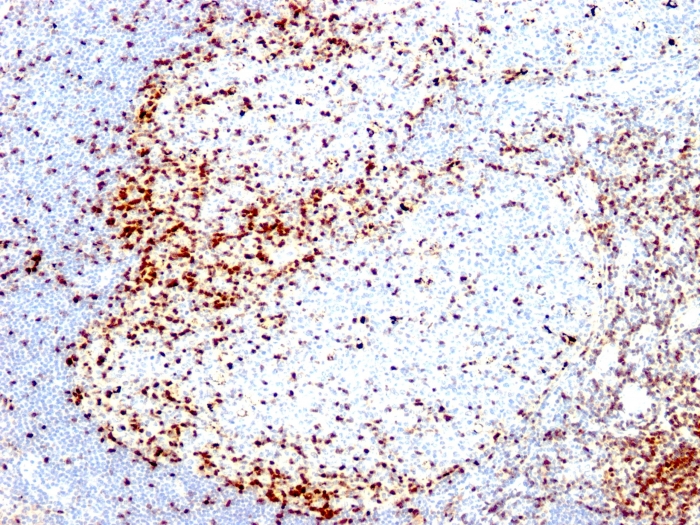

ZAP70 is a 70kDa protein tyrosine kinase found in T-cells and natural killer cells. Control of this protein translation is via the IgVH gene.In Western blotting of whole cell lysates of normal peripheral blood mononuclear cells, the antibody labels a band corresponding to ZAP70. In Western blotting of whole cell lysates of CD19-positive Purified leukemia cells from patients with Ig-unmutated and Ig-mutated CLL, the antibody labels a band corresponding to ZAP70 in the Ig-unmutated CLL samples, whereas no band is observed in the Ig-mutated CLL samples. In Western blotting of cell lysates of Jurkat cells (T-lymphoblastic cell line), the antibody labels a band of 70kDa protein. In Western blotting of cell lysates of A431 cells (carcinoma cell line), no band is observed. ZAP70 protein is expressed in leukemic cells of approximately 25% of chronic lymphocytic leukemia (CLL) cases as well. Anti-ZAP70 expression is an excellent surrogate marker for the distinction between the Ig-mutated (anti-ZAP70 negative) and Ig-unmutated (anti-ZAP70 positive) CLL subtypes and can identify patient groups with divergent clinical courses. The anti-ZAP70 positive Ig-unmutated CLL cases have been shown to have a poorer prognosis.